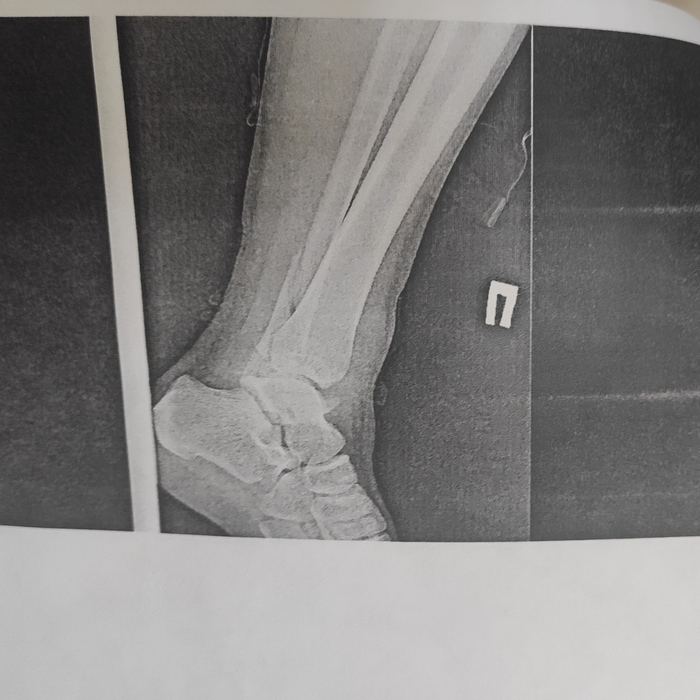

Я мужчина. 30 с лишним лет. Примерно неделю назад у меня начались боли в правом голеностопе в надетой разношенной обуви. Для понимания ниже прикрепил фото, где красным примерно отметил области, включая пальцы, где болит. Фото не моей ноги, взято из интернета, если нужно, то пришлю своей.

Боль выражается в чувстве сдавленности пальцев ноги (третий, четвёртый и мизинец) и области выше от пальцев, где обведено красным. Как будто правая обувь стала вдруг не по размеру. Хотя попробовал надеть уже 4 пары разной обуви, которая ранее нормально носилась и не вызывала этих ощущений. Но со всеми 4 разношенными парами разной обуви это проявляется. Правая нога внутри обуви в пределах колодки двигается немного права и влево, пальцы приподнимаются. То есть обувь не впритык к ноге. Но чувствуется скованность и болезненность. Во время подъёма пальцев в обуви в правой ноге может возникнуть ощущение легкого покалывания подушечек указанных пальцев, небольшое онемение и прохлада. Суставы пальцев на ноге при этом не болят.

Боль в проблемных зонах не острая, а давящая, при нажатии руками на разные участки стопы и пальцев тоже острой боли нет. Травм и ушибов правой ноги не было. Наступать на саму стопу не больно, нигде ничего не отдаёт, стопа и пальцы вне обуви свободно двигаются, поворачиваются и сгибаются без боли. Отёков, припухлостей, наростов на мой немедицинский взгляд нет, посторонние тоже говорят, что внешне никаких подозрительных изменений на правом голеностопе нет. На коже никаких пятен, образований и т. д. также нет.